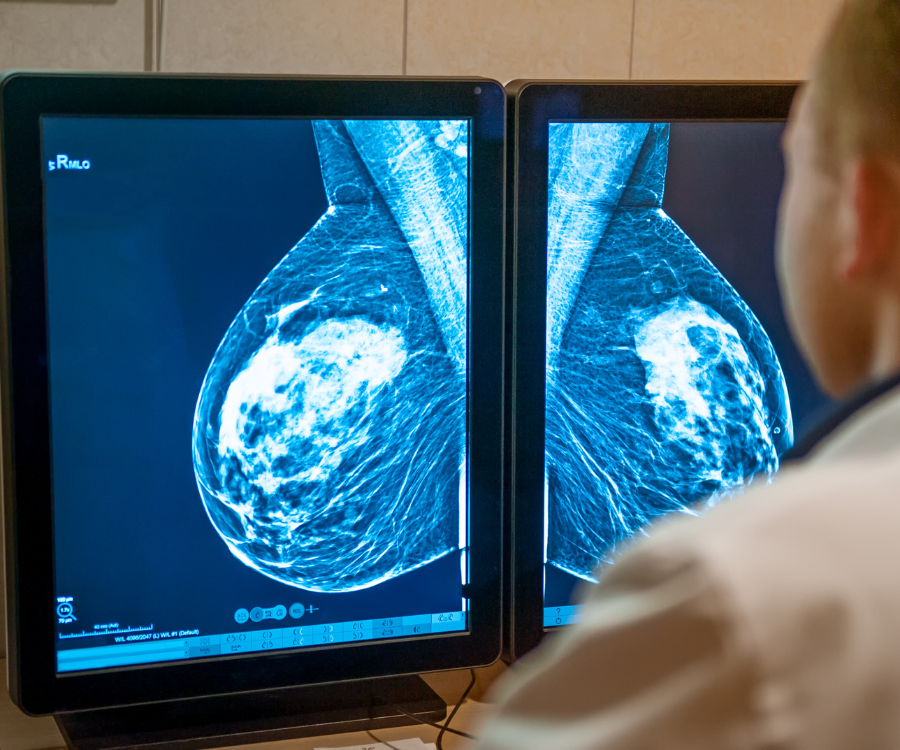

- A mammogram is a specialized, low-dose X-ray examination of the breast that uses a dedicated machine to take multiple images from different angles. It’s specifically designed to detect early signs of breast cancer, even before a lump can be felt.

- The Procedure: A certified technologist will position your breast in the machine. Your breast will be compressed between two plates for a few seconds while the X-ray images are taken. This compression is necessary to get a clear image with a low dose of radiation. While it can be uncomfortable, it is quick and not typically painful.

- Afterward: The entire process usually takes less than 20 minutes. The images are then reviewed by a radiologist. You and your doctor will receive the results, and if anything looks suspicious, you may be called back for a diagnostic mammogram or another test to get a closer look.